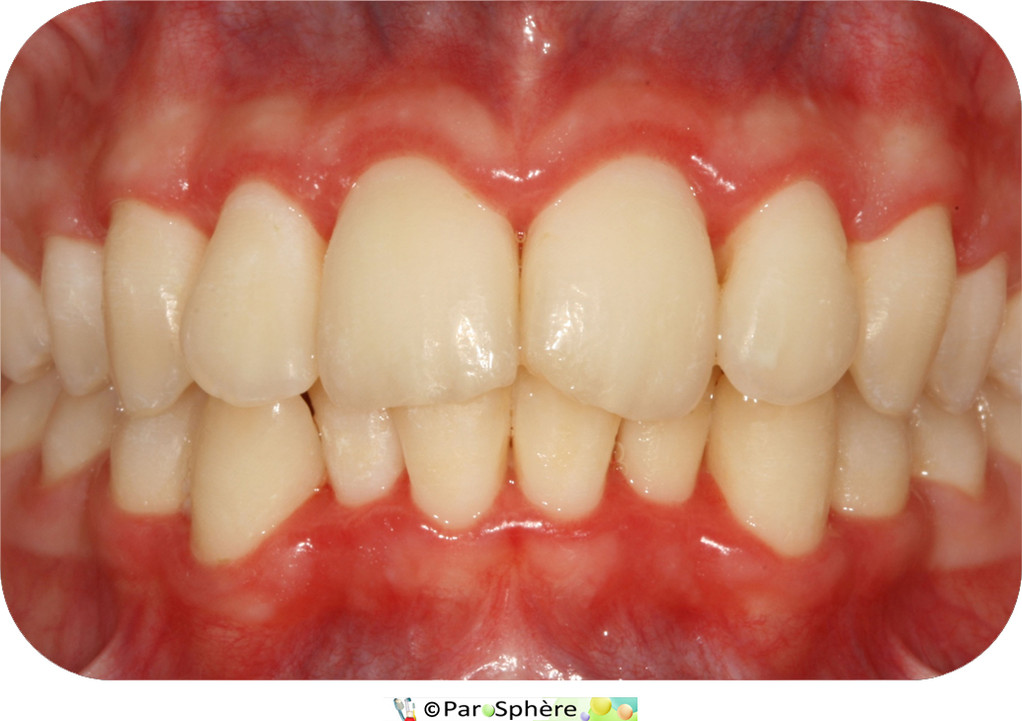

La première photographie montre une vue clinique des secteurs antérieurs avant traitement.